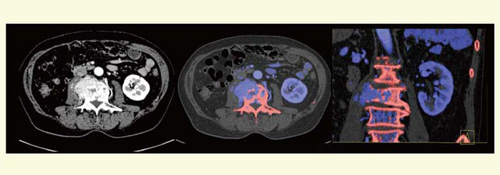

石灰化を赤色,造影剤を青色に分類すると,造影された血管と石灰化プラークが明瞭に識別できる。腹部領域に応用すると,肝細胞がんの骨転移例では,濃染する腫瘍と骨が視覚的にわかりやすく表示され,識別可能となる(図3)。

図3 肝細胞がんのhard plaque画像